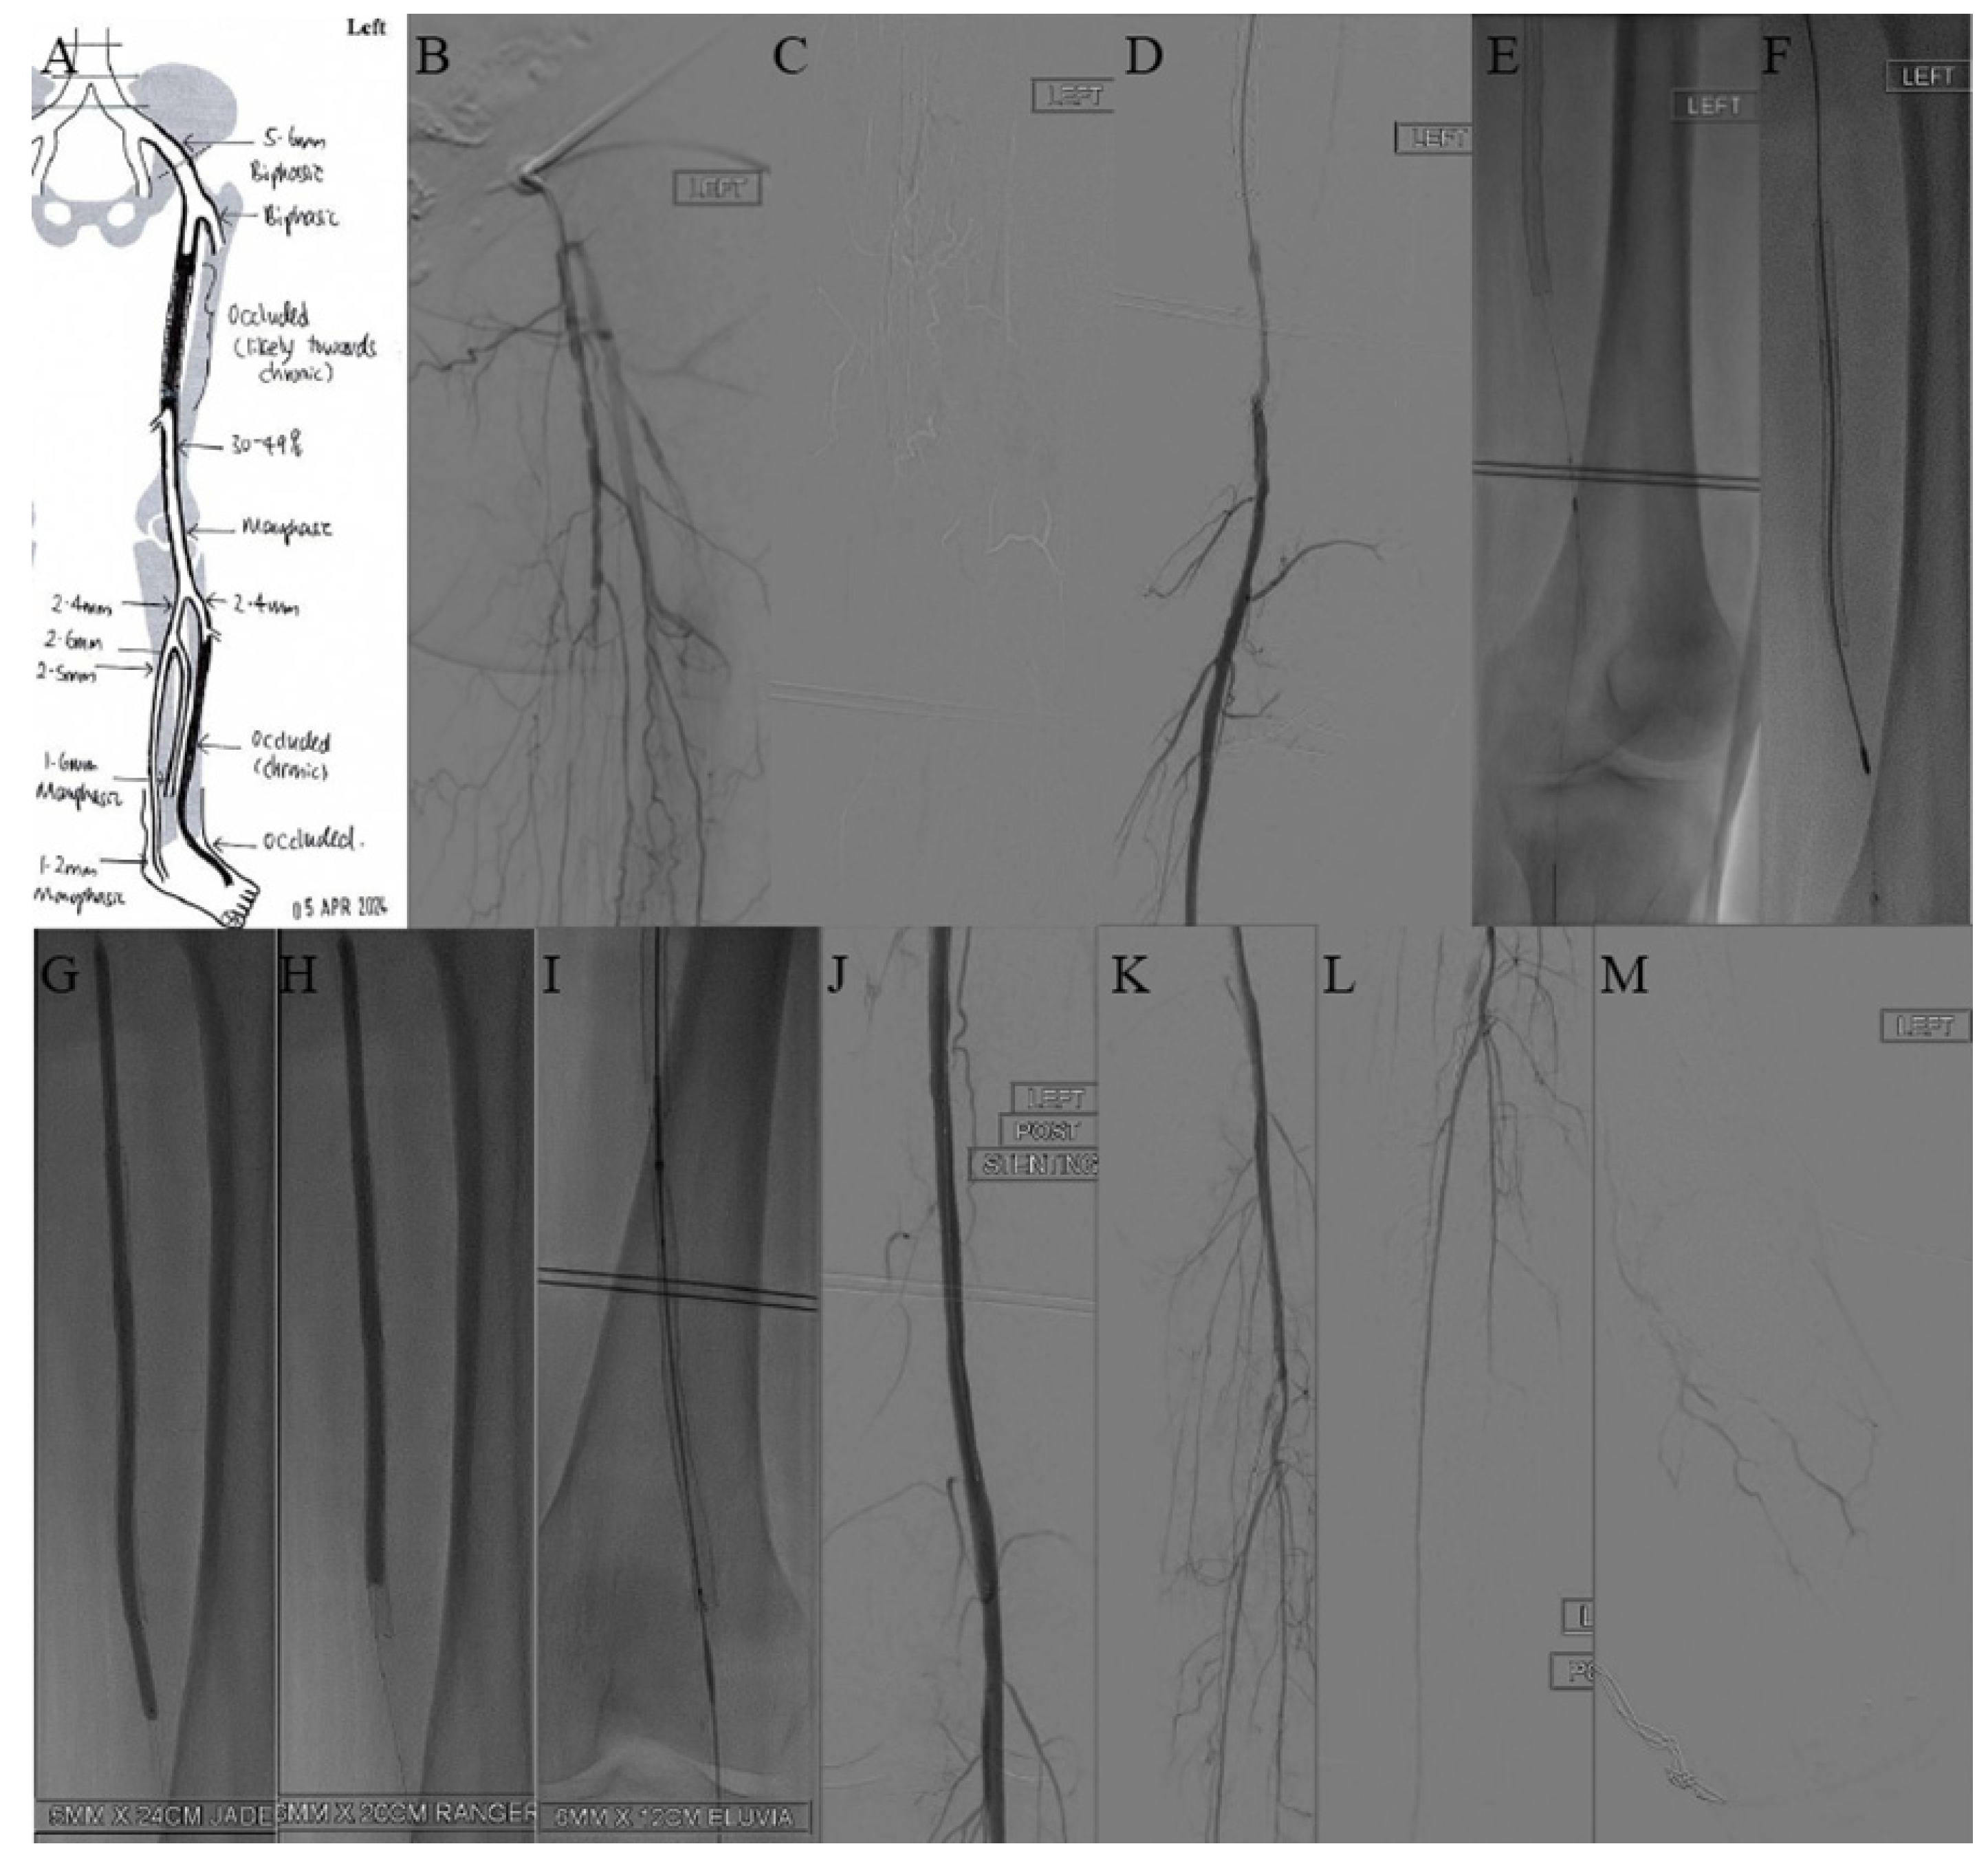

2.3. Case 3—A Case of Severely Calcified Femoral–Popliteal Disease with Extensive Circumferential Calf Wounds